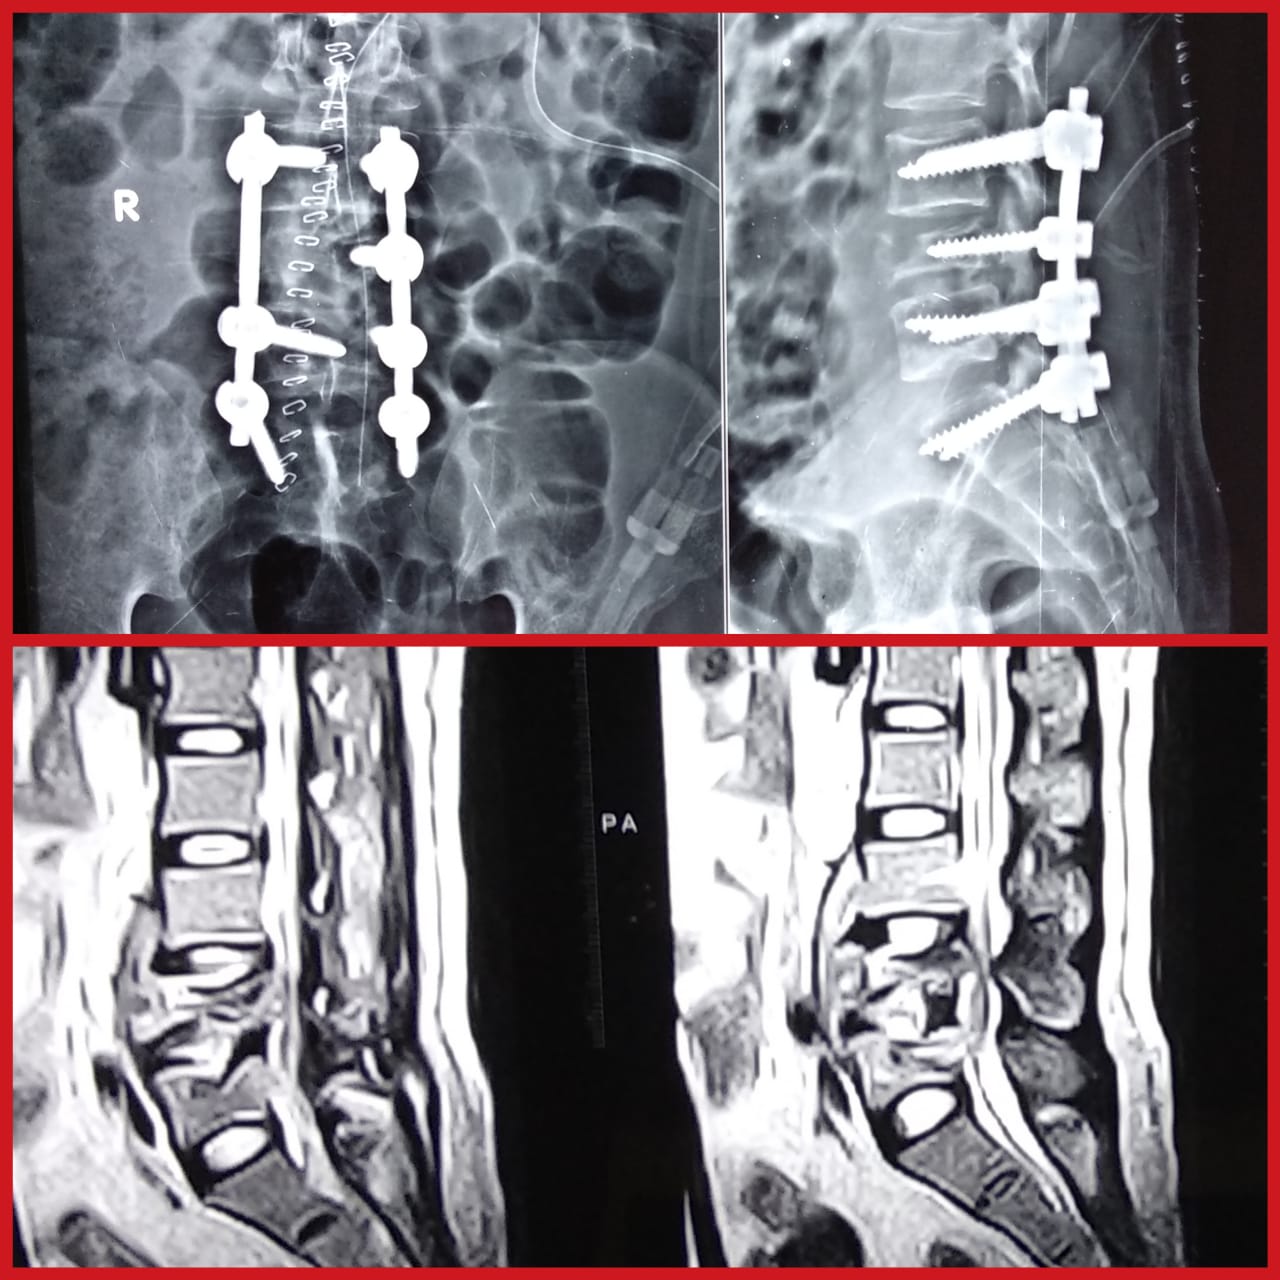

Dr Rahul Chaudhari-Best Spine Surgeon in Pimple Saudagar,Pune Online Clinic-Pimple Saudagar 411027 | Visiting Clinic-7 Orange Hospital, Pawana Nagar Housing Society, Chinchwad, Pimpri-Chinchwad, Maharashtra 411033 +918048032706 rahulc.ortho@gmail.com

Dr Rahul Chaudhari-Best Spine Surgeon in Pimple Saudagar,Pune Online Clinic-Pimple Saudagar 411027 | Visiting Clinic-7 Orange Hospital, Pawana Nagar Housing Society, Chinchwad, Pimpri-Chinchwad, Maharashtra 411033 +918048032706 rahulc.ortho@gmail.com

Dr Rahul Chaudhari-Best Spine Surgeon in Pimple Saudagar,Pune Online Clinic-Pimple Saudagar 411027 | Visiting Clinic-7 Orange Hospital, Pawana Nagar Housing Society, Chinchwad, Pimpri-Chinchwad, Maharashtra 411033 +918048032706